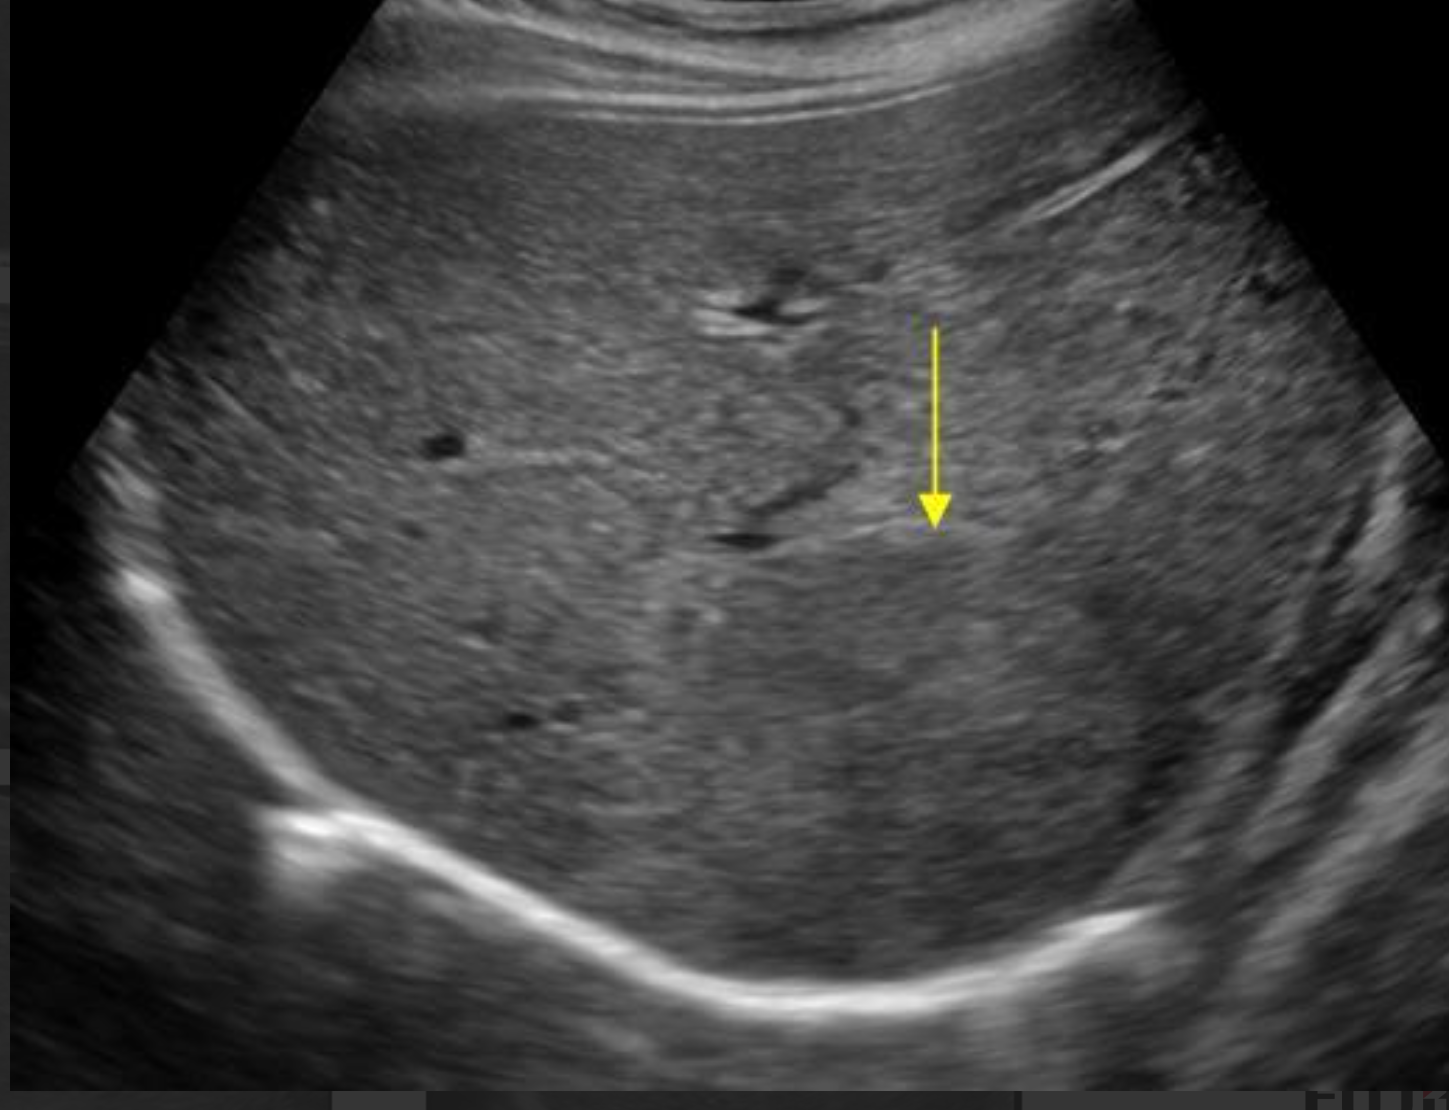

Which of these liver masses/nodules is a malignant tumor.

B-mode ultrasonography is highly sensitive for detecting focal liver lesions but is poorly specific for lesion type. Hepatic masses may appear:

• Hypoechoic, hyperechoic, or mixed echogenicity

• Well-marginated or irregular

• Solitary or multifocal

Importantly, echogenicity does not correlate reliably with malignancy. Multiple studies have demonstrated substantial overlap in the sonographic appearance of benign nodules, primary hepatic tumors, and metastatic lesions (Nyland et al., 2002; O’Brien et al., 2004)

In a large retrospective study of canine liver tumors, no consistent B-mode ultrasonographic features reliably differentiated hepatocellular carcinoma, cholangiocarcinoma, sarcoma, or metastatic lesions, aside from lesion distribution (O’Brien et al., 2004). Hepatocellular carcinomas were more likely to be solitary, whereas sarcomas and metastases were more often multifocal, but significant overlap existed.